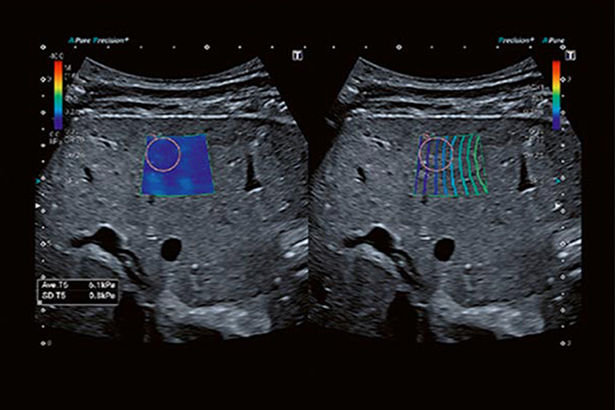

剪切波技術能夠定量測量并實時顯示組織彈性,從腹部、小器官到前列腺檢查,可適應多種臨床需求。